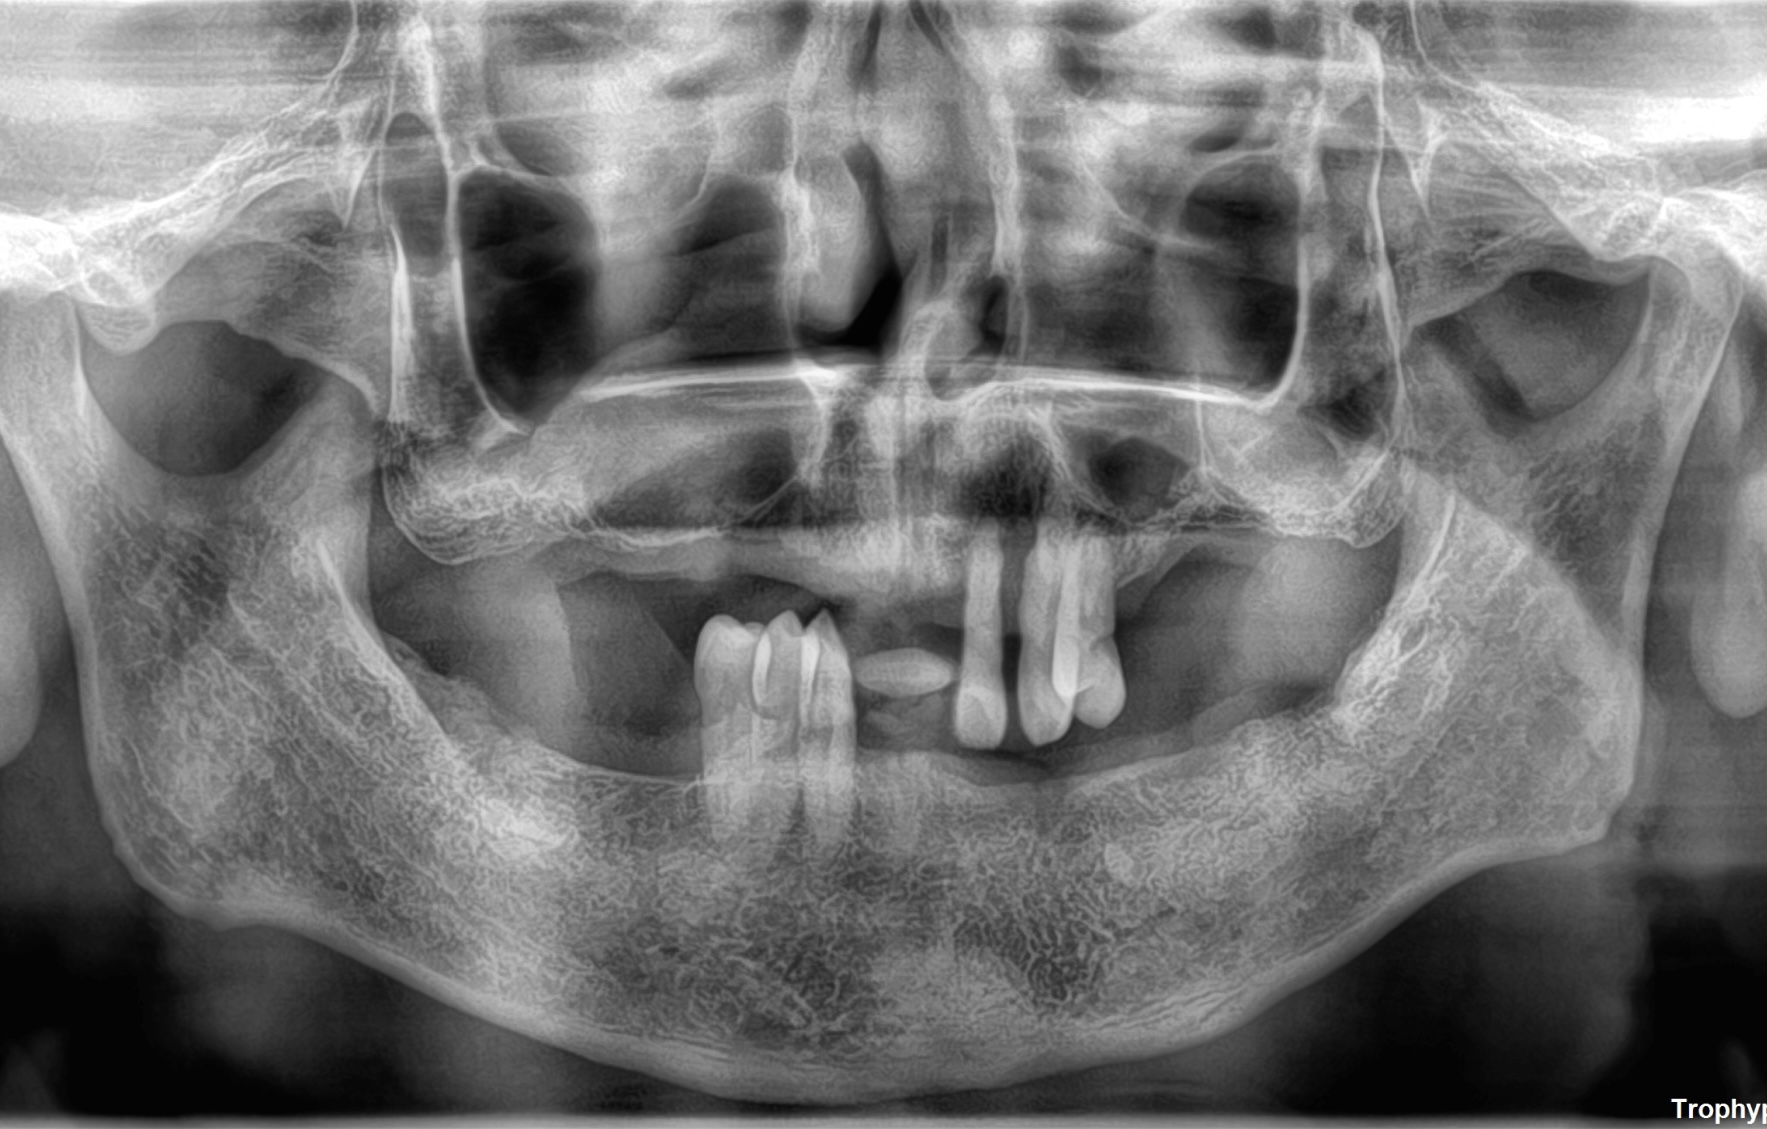

CASE

2